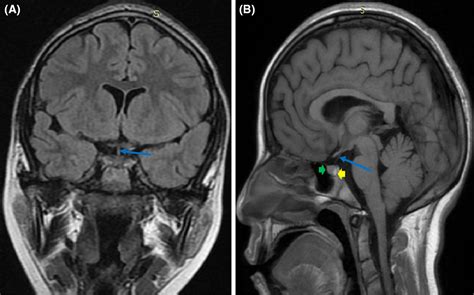

When investigating the pituitary with infundibular stalk, clinicians often look at the thickness and signal intensity of the stalk on imaging tests like MRIs. A thickened stalk can be an early indicator of inflammatory processes, infiltrative diseases, or tumors, emphasizing why this tiny anatomical feature is so vital for diagnostics.

Medical imaging has transformed our ability to examine the pituitary with infundibular stalk in a non-invasive manner. Modern high-resolution MRI scans are the gold standard for identifying potential pathology in this region. Radiologists specifically look for symmetry, the position of the optic chiasm, and the integrity of the stalk itself.

• Pituitary Adenomas: Benign tumors that can grow and push against the stalk, causing hormonal imbalances.

Because the stalk is so close to the optic nerves, any mass or swelling in this area can lead to "bitemporal hemianopsia," or the loss of outer peripheral vision. This is why patients with pituitary-related concerns often require both a hormonal blood panel and a comprehensive ophthalmological examination.